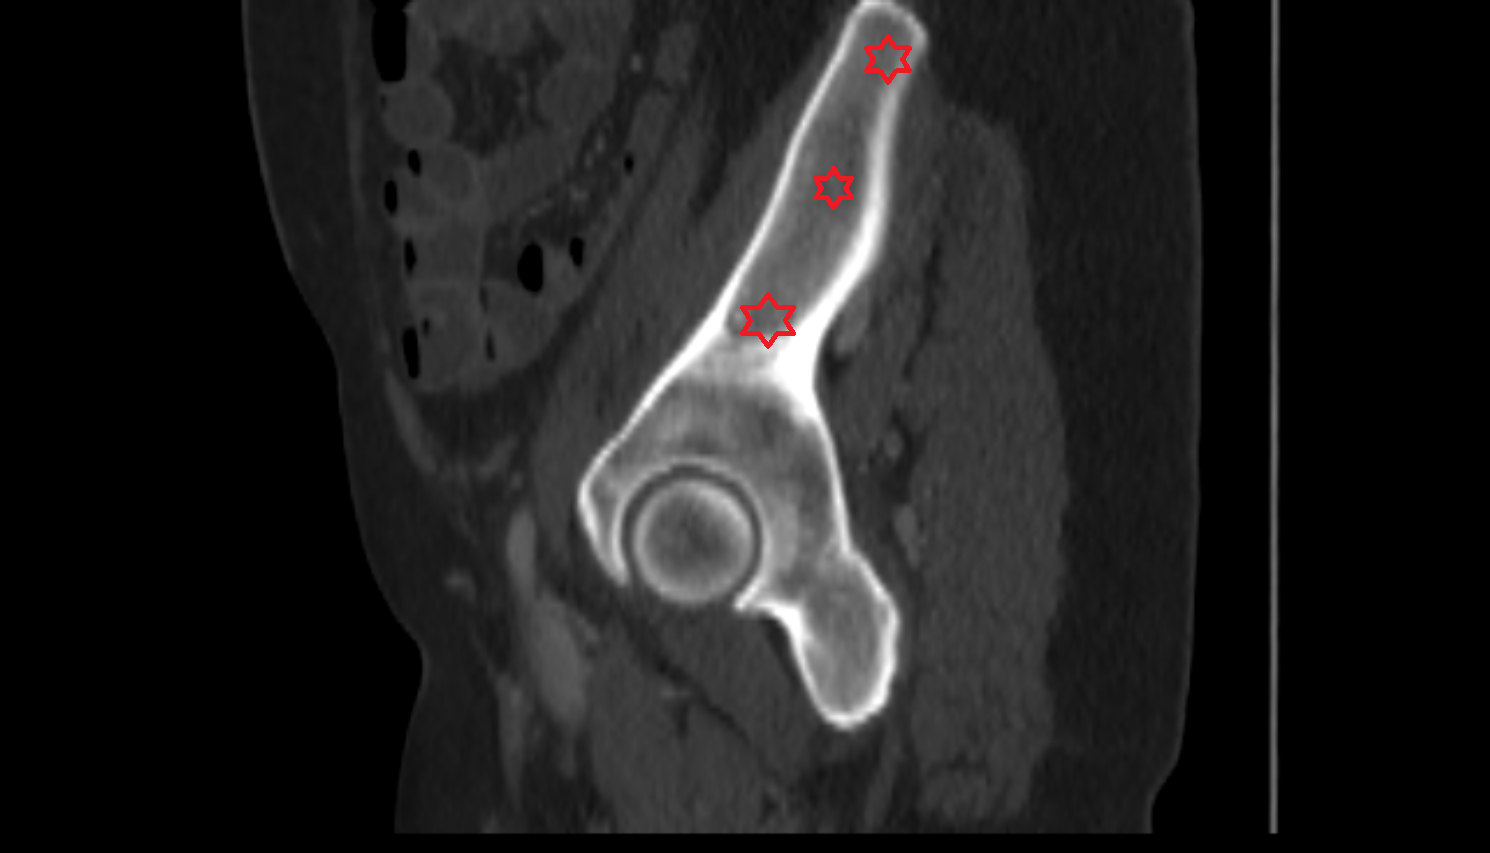

- Head of femur

- Neck of femur

- Greater trochanter

- Acetabulum

- Body of ilium

- Ilium bone

- Ala of ilium (wing of ilium)

- Iliac crest